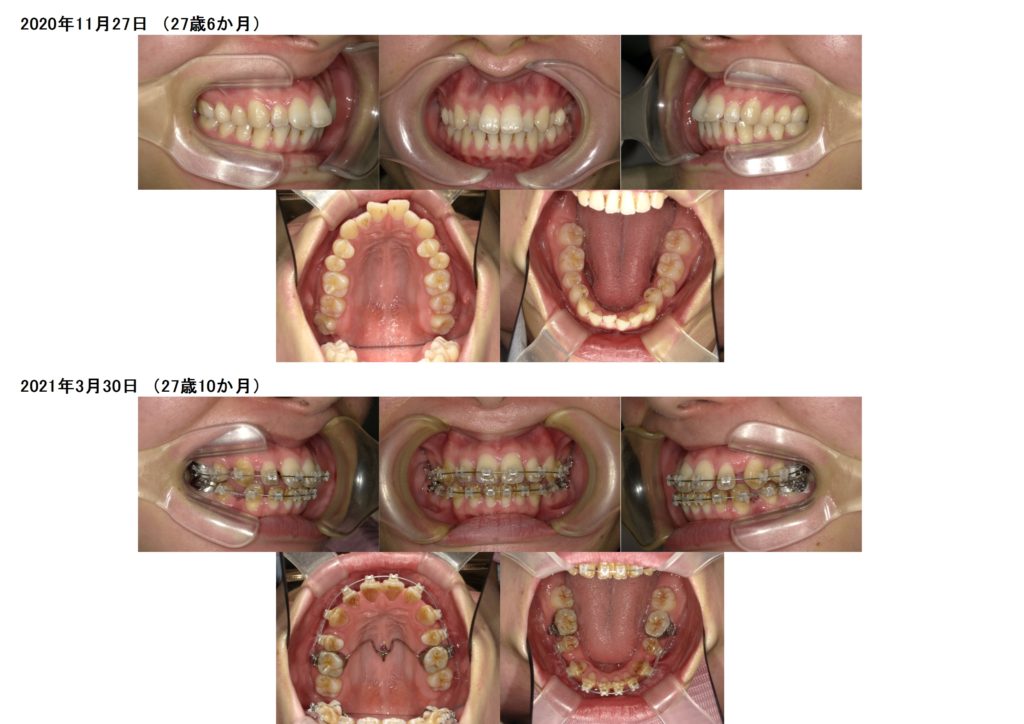

今回はフルブラケット装置(セルフライゲーションシステム)での上下抜歯の治療例のご紹介です。

上顎にアンカースクリューを1本、パラタルバーが入っています。

初診時の検査から約4カ月。装置を着けてからそんなに期間は経過していませんがしっかりと歯が動いているのが分かります。

この患者様は奥歯を動かないように固定するためにアンカースクリューとパラタルバーを入れています。